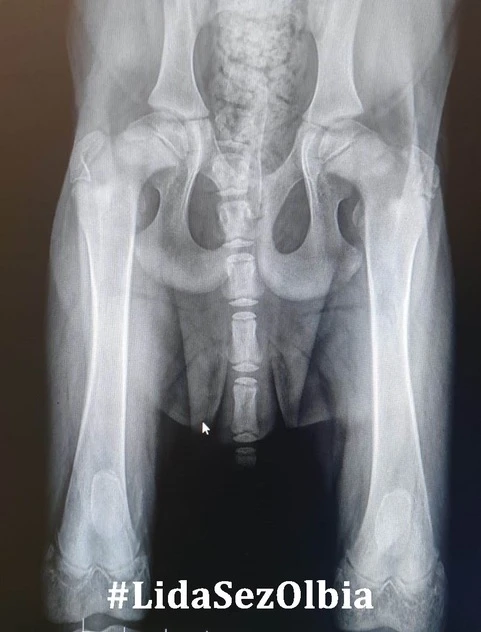

Nach einer Phase der leichten Besserung kamen nun die Beschwerden zurück, aber mit voller Wucht – beide Hinterbeine von Masai versteiften sich durch eine anhaltende Muskelkontraktion.

Blut wurde abgenommen und die Ergebnisse bestätigten den Verdacht:

Neosporose (und Toxoplasmose) positiv.

Die Neosporose der Junghunde ist gekennzeichnet durch progressive, aszendierende Paralyse und Parese der hinteren Extremitäten und ist auch als sogenanntes Neuromuskuläres Syndrom bekannt.

Es hilft hier nur, die betroffenen Extremitäten manuell zu bewegen. Ein sehr schmerzhaftes Prozedere für den Hund, weshalb Masai nun deshalb für die Anwendungen immer sediert wird.

Führen all diese Maßnahmen nicht zum Erfolg, so bleibt nur noch die Amputation der Hintergliedmaßen.